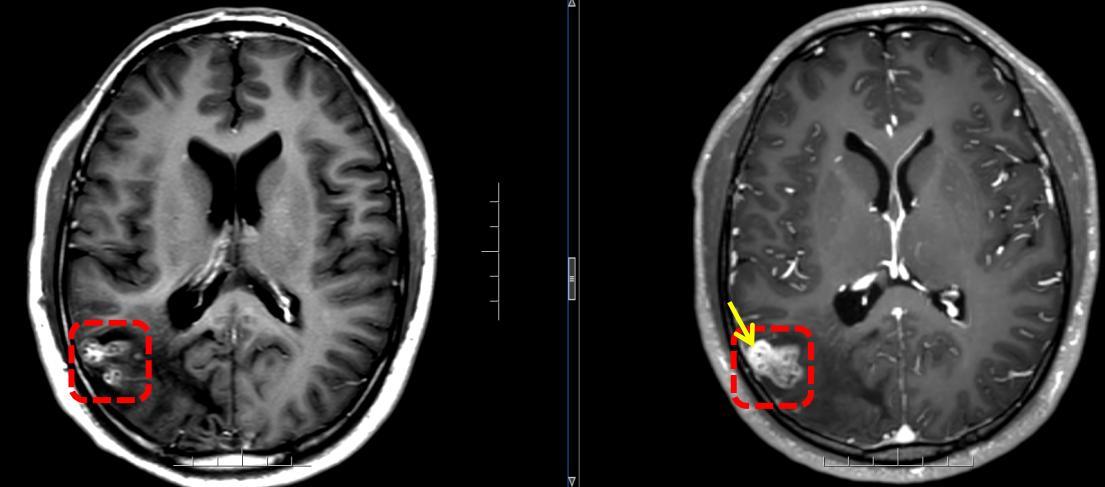

接诊的该院神经外八科二区副主任陈俊喜和王艮波主治医师,对比李正历次头部影像,发现病灶不仅位置移动,还呈现“隧道征”,高度指向脑裂头蚴病。后续血清检查结果也提示裂头蚴抗体阳性。

“除近期的癫痫大发作,患者此前频繁出现视野闪光、画面感,其实也是癫痫发作。”陈俊喜解释,从影像来看,虫体已从大脑深部爬至表层,正是手术取出的好时机。于是,他带领团队快速安排了裂头蚴捉取手术,成功从李正脑内取出一条长约18cm的活虫。